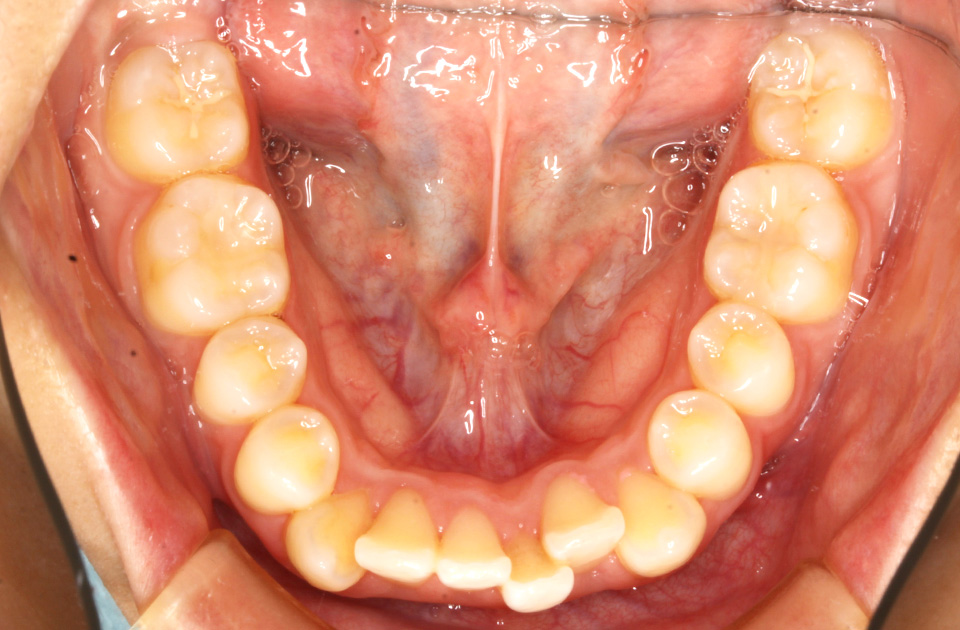

矯正前 下顎

矯正後 下顎